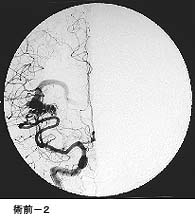

(1)破裂脳動脈瘤に対するGDC(コイル)塞栓術

*術後 コイルにより動脈瘤が写らなくなりました。